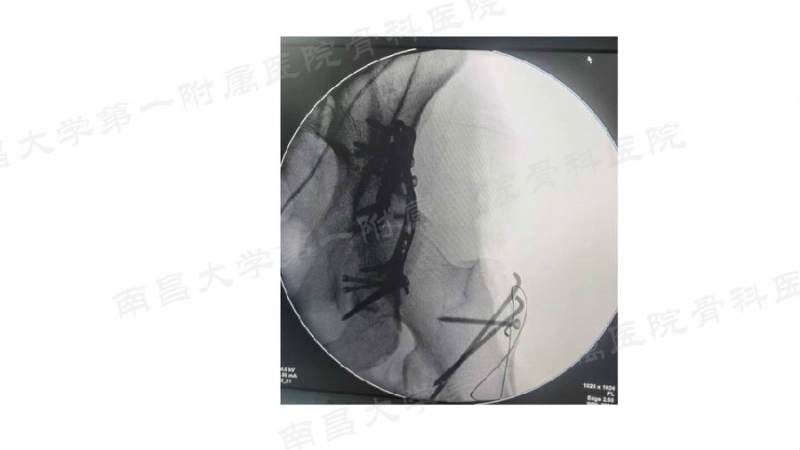

病例一

病例二

病例三